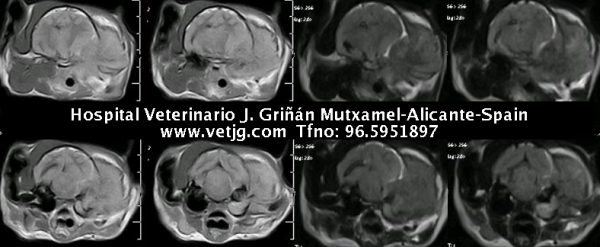

La resonancia magnética indica la etiología del proceso: neoplasia ósea que invade bulla timpánica, articulación temporomandibular, hueso temporal y hemisferio cerebral izquierdos |

Resonancia de otro gato con el mismo cuadro clínico e imagenológico, pero más avanzado (estaba dos años con gotas para la "otitis") |